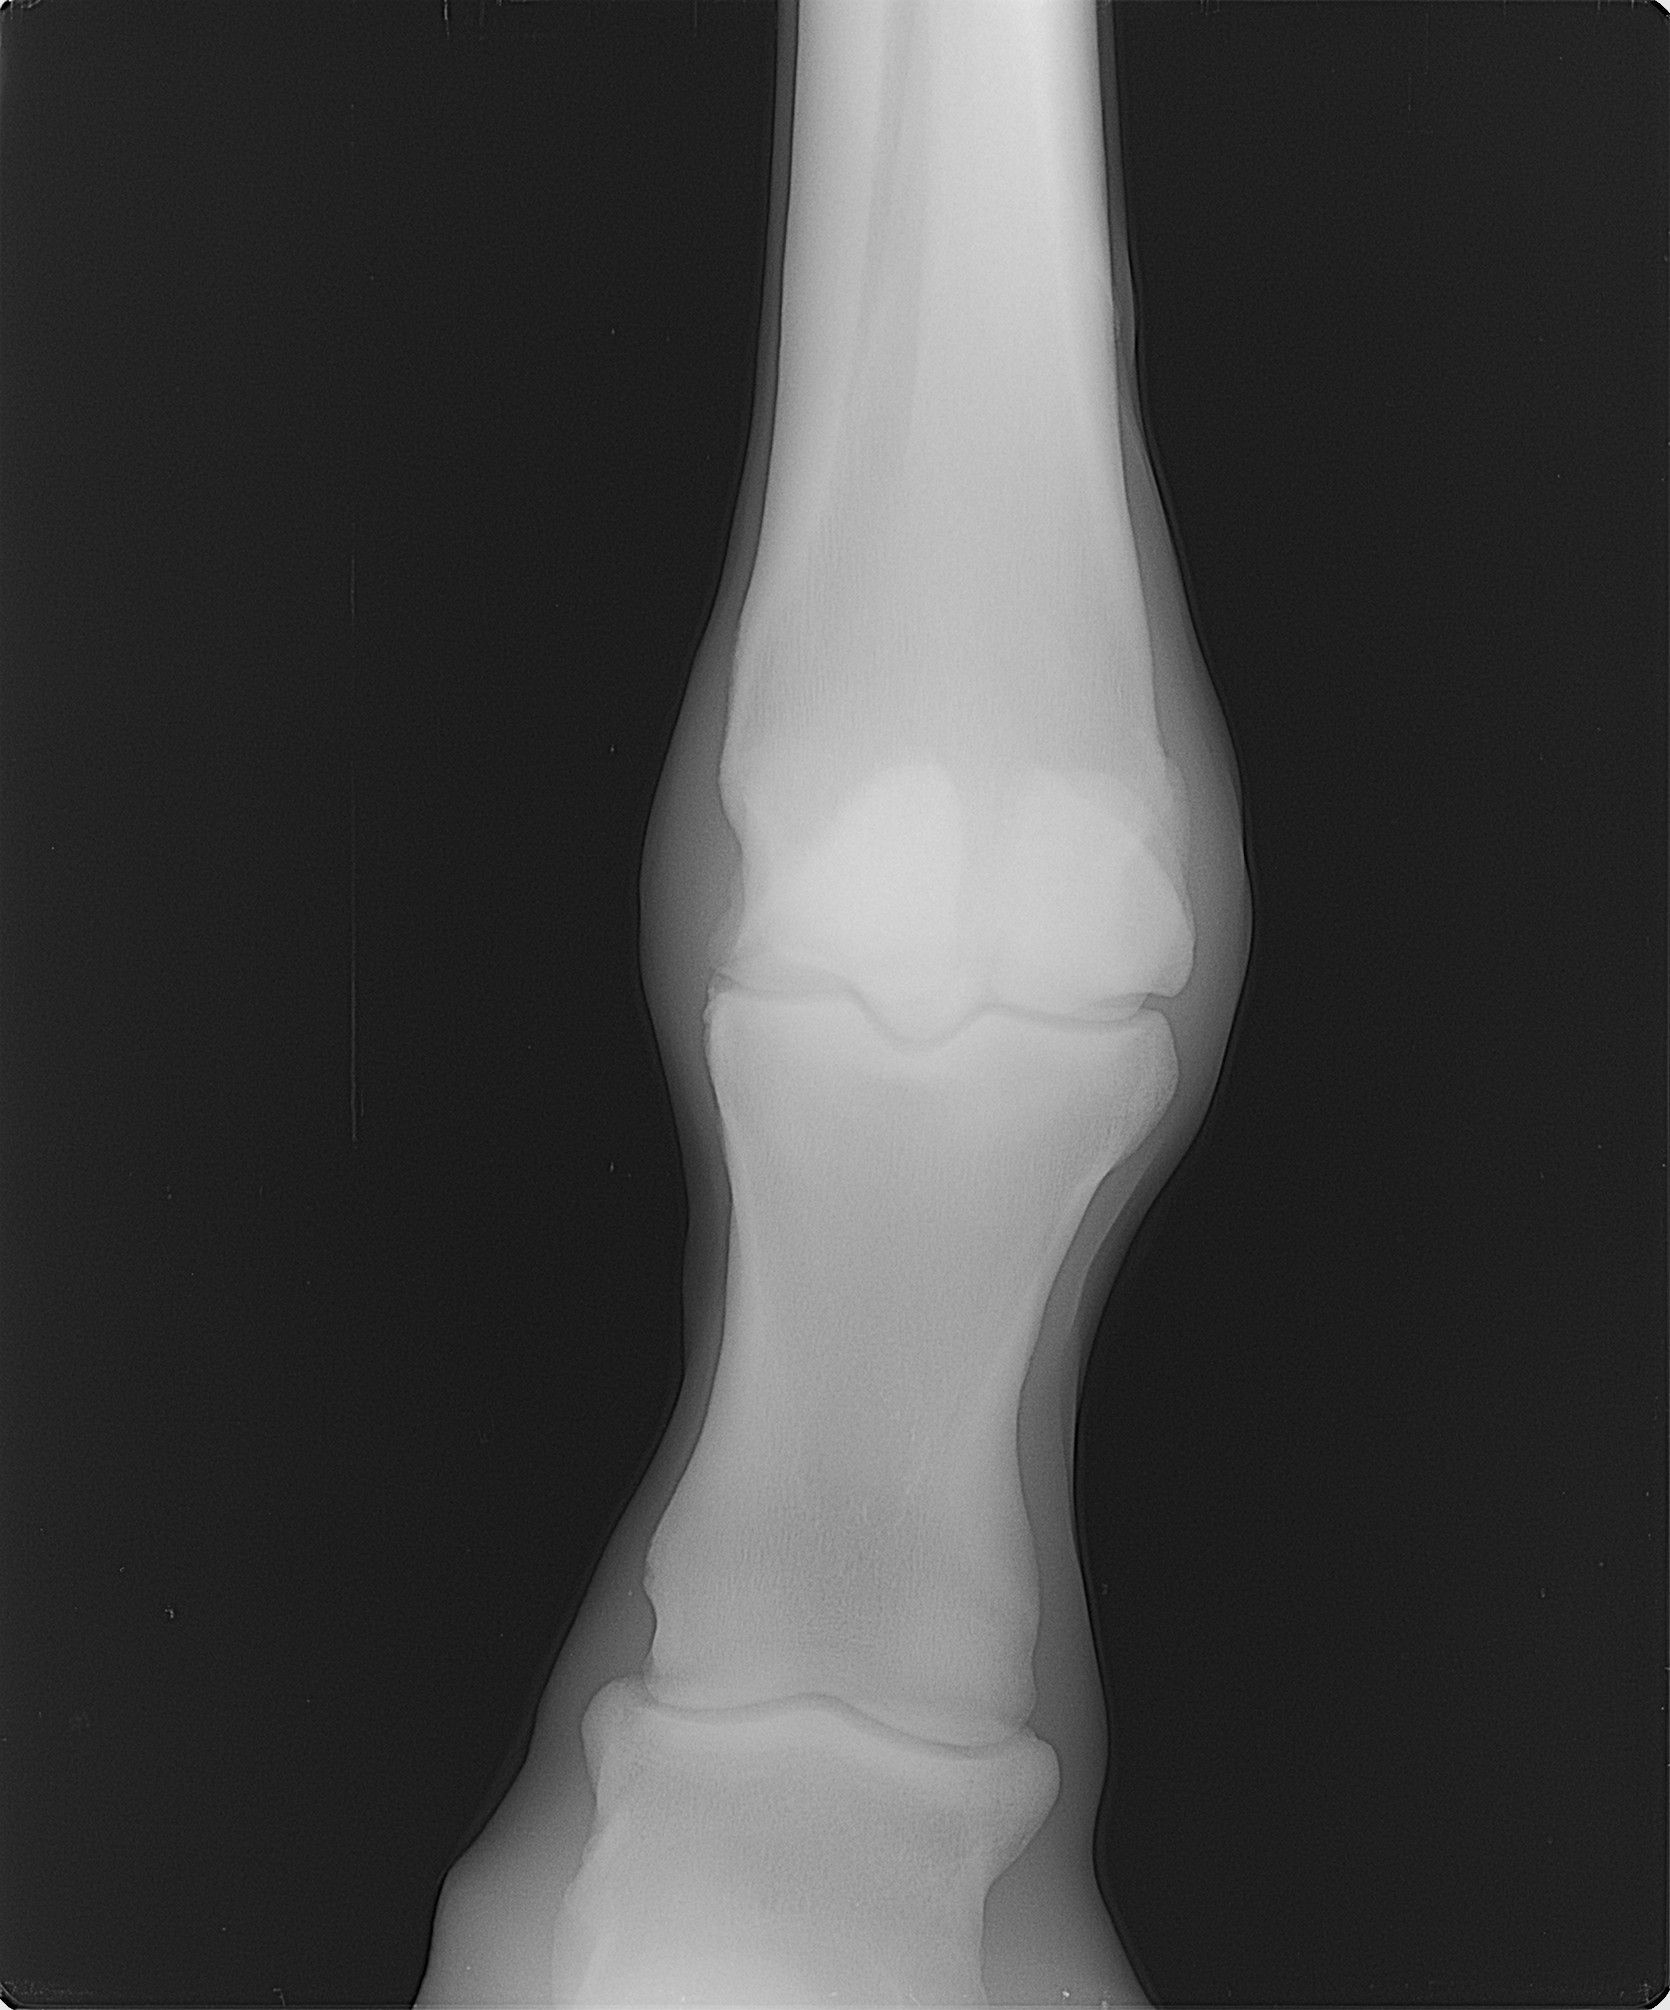

本馬は一時、坂路でハロン18秒ペースのキャンターまでペースアップしていたのですが、右トモが弱いこと、右前肢の蹄踵部を潰しやすいことが影響して順調に進めることができませんでした。2019年2月1日に右トモに跛行を呈したためレントゲン検査を実施したところ、右後肢第三中足骨遠位端亀裂骨折を発症していることが判明しました。現在は常歩レベルでは歩様に問題ないためウォーキングマシン運動を再開していますが、JRAでのデビューは厳しいと判断して今回のサラブレッドオークションへ出品することにいたしました。

2月1日に右トモが跛行したためレントゲンを撮ったところ、右後肢第三中足骨遠位端亀裂骨折を発症していました。レントゲン検査から1ヵ月ほど経過した現在は、速歩ではまだ跛行気味ですが常歩では問題ないため、現在はウォーキングマシンに入れて1時間歩かせているところです。右前肢の蹄踵部を潰しやすく、潰れると跛行してしまうため、エクイパックを充填して潰れないように処置しています。もともと右トモにも弱さがあって順調に進めることができておらず、ここから立ち上げてスムーズにいったとしても、デビューを迎えるのは夏以降になるでしょう。なお、右前の手根腱鞘部にはオステオコンドローマ(骨軟骨腫)があります。(EISHIN STABLE・渡辺場長)

※2019年2月1日に右後肢に跛行を呈したためレントゲン検査を実施したところ、右後肢第三中足骨遠位端亀裂骨折を発症していることが判明しました。

※右前の手根腱鞘部にオステオコンドローマ(骨軟骨腫)を発症しています。